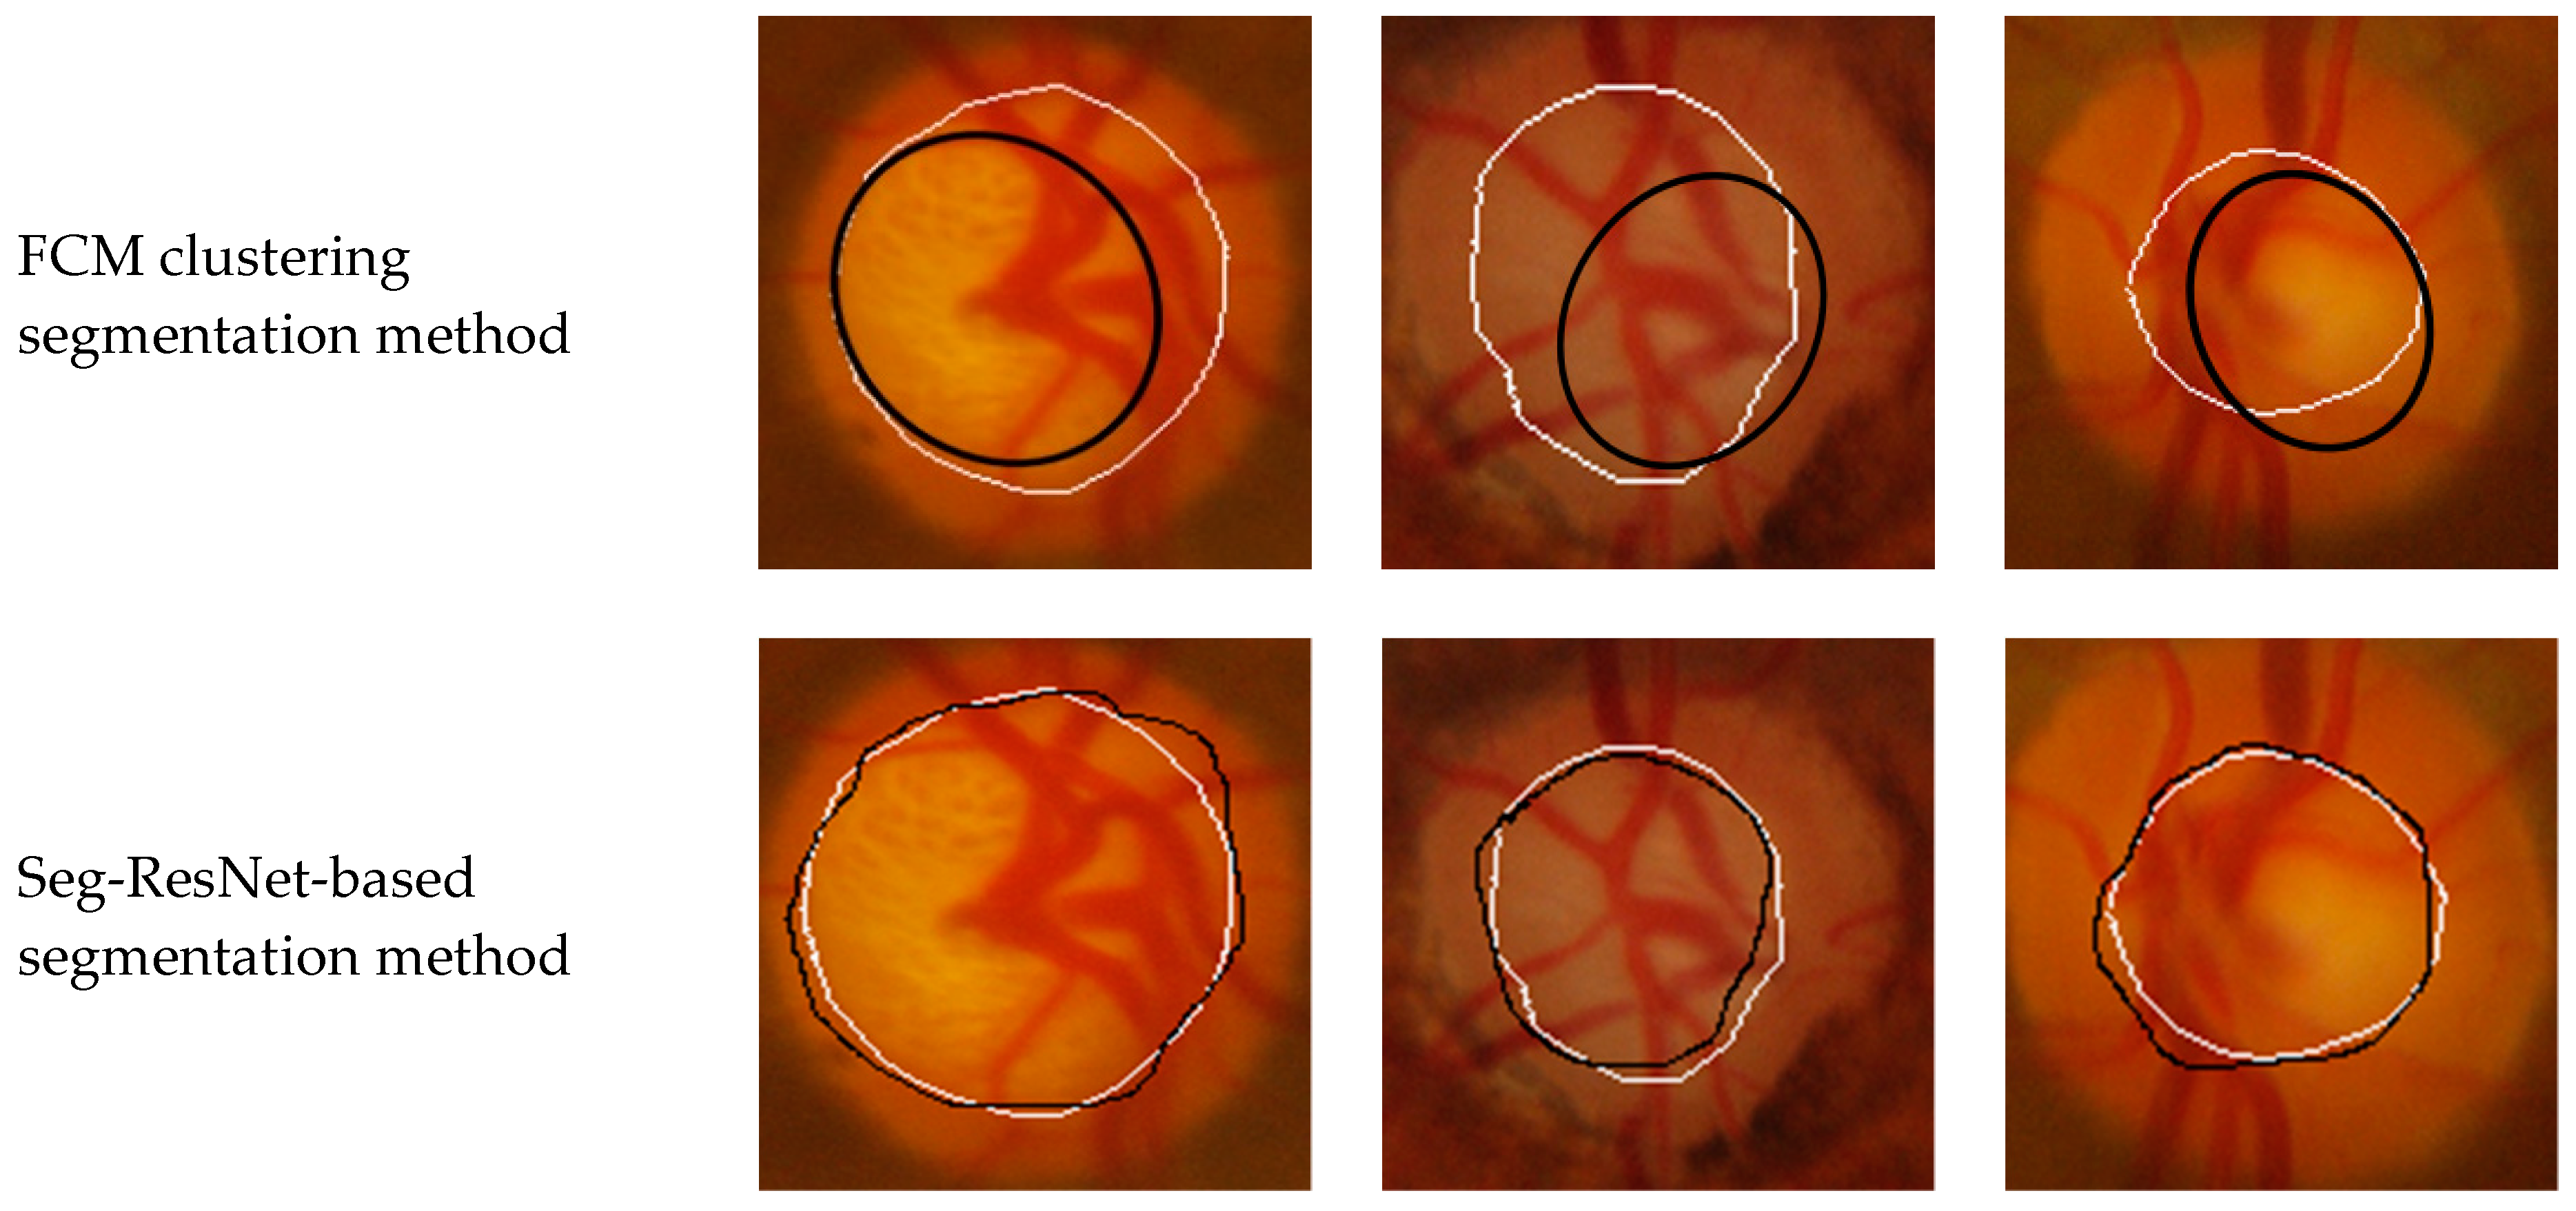

To verify the performance of the Seg-ResNet network-based optic cup segmentation method proposed in this paper, we compared our method to the FCM cluster segmentation method. The segmentation results are shown in Figure 9 and Figure 10.

• GlaucomaRepo database segmentation results.

• Drishti-GS database segmentation results.

The optic cup segmentation method, based on FCM clustering, fully considered the brightness information of the image and the characteristics of the blood vessel bending point falling on the edge of the optic cup. However, due to the complicated fundus image, the extraction of the optic cup needed to undergo a series of preprocessing steps, including disc segmentation, region of interest extraction, blood vessel extraction, blood vessel bending point detection, optic cup rough segmentation, and ellipse fitting. Each step was sequential, i.e., each operation was based on the previous operation. If the result of an operation was inaccurate, then it would have had a greater impact on the final result. The division of the optic cup by conventional methods would inevitably be compounded by each pre-processing operation. Figure 9 and Figure 10 show that the conventional method could not accurately divide the optic cup in cases of low cup plate contrast and severe vascular occlusion, while the segmentation effect on the Drishti-GS data set was poor. The results were likely affected by the fact that the GlaucomaRepo data set and the Drishti-GS data set were taken from different fundus cameras, thus the imaging quality varied greatly. The overall gray value of the Drishti-GS data set was low, the vascular occlusion was severe in most images, the method used for filling the neighborhood pixels was not obvious, the FCM optic cup clustering was affected by vascular interference, and the segmentation effect was below average. Traditional image processing techniques are difficult to change between these two data sets, so traditional image processing technology is less robust than the optic cup segmentation method. The depth-based learning method based on deep learning methods used a large number of data sets, where each image was taken from different cameras in different shooting environments. Thus, the feature extraction method had strong adaptability and also showed excellent segmentation effects in different test sets. Figure 9 and Figure 10 show optic cup segmentation using a depth-based learning method, which not only learned the brightness characteristics of the optic cup, but also learned the characteristics of blood vessel bending at the edge of the optic cup. This was seen in both the GlaucomaRepo data set and the Drishti-GS data set; this information could be used to accurately divide the optic cup. Table 3 and Table 4 compare the segmentation performance of the deep learning methods using two different traditional databases. Overall, optic cup segmentation based on depth-based learning methods had higher precision and robustness over the traditional image processing technology.

Figure 9. GlaucomaRepo database segmentation results comparison using the Seg-ResNet-based method and the FCM clustering optic cup segmentation method.

Symmetry 11 00933 g009aSymmetry 11 00933 g009b